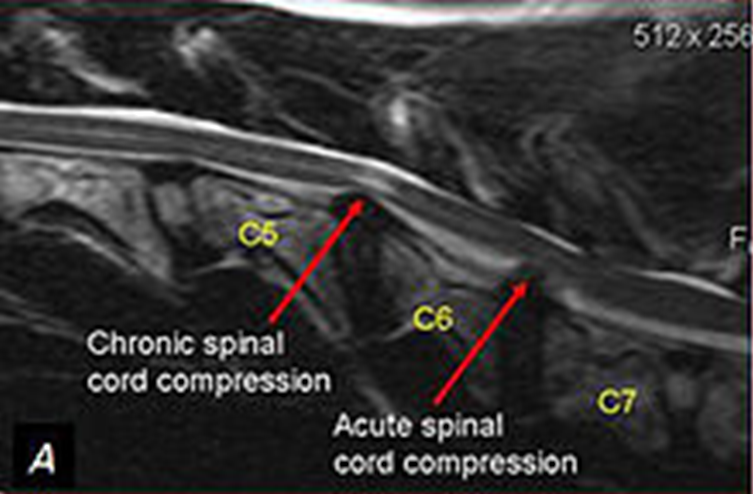

图3 马Wobbler综合征的颈椎MRI,显示C5/6,C6/7水平脊髓受压